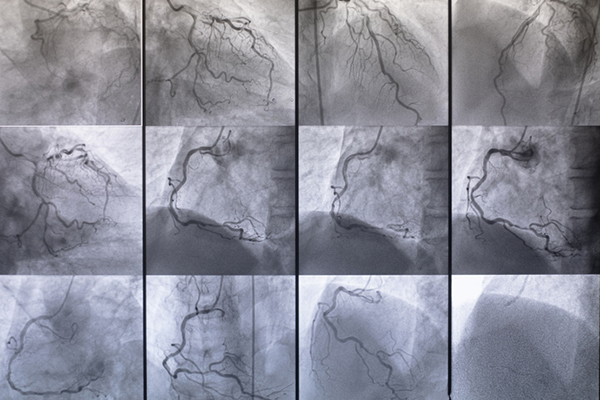

Coronary angiography is a radiological examination which lets you visualize the coronaries. The latter, in actual fact, will be the topic of shrinkage as a consequence of fats and calcium depositsThese build-ups lower blood move inside the vessels, which causes it chest ache and, in case of whole occlusion, myocardial infarction. We recall that the narrowing of the arteries is because of the thickening of the inner wall of the vessels because of the formation of an atherosclerotic plaque, and that the continual irritation of the arteries, brought on by this thickening, known as atherosclerosis. There coronary angiography of the guts, subsequently, it is a vital examination why permits to grasp if the coronaries are free or if they’re obstructed.

- Due to X-ray might be acquired photos of the precise and left coronary artery (this examination additionally permits to visualise the left ventricle and to confirm its capacity to contract).